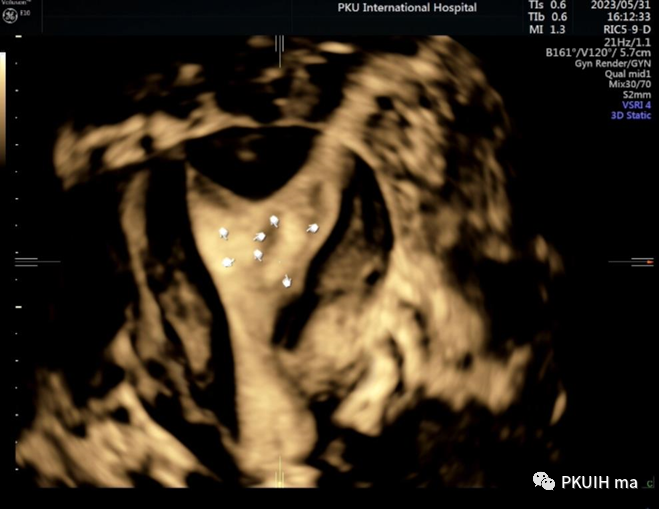

三维超声显示弓形子宫畸形和子宫内膜息肉